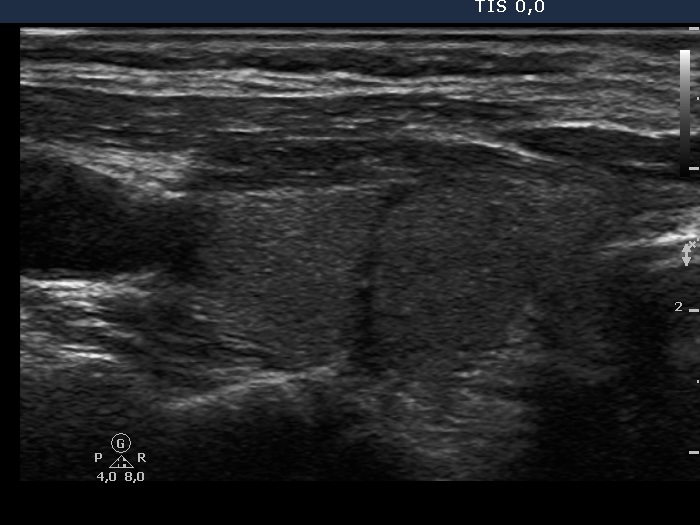

Ultrasonography. The thyroid was composed of circumscribed echonormal and minimally hypoechogenic areas divided by fibrous tissue. None of these areas corresponded to a nodule in a pathological sense.